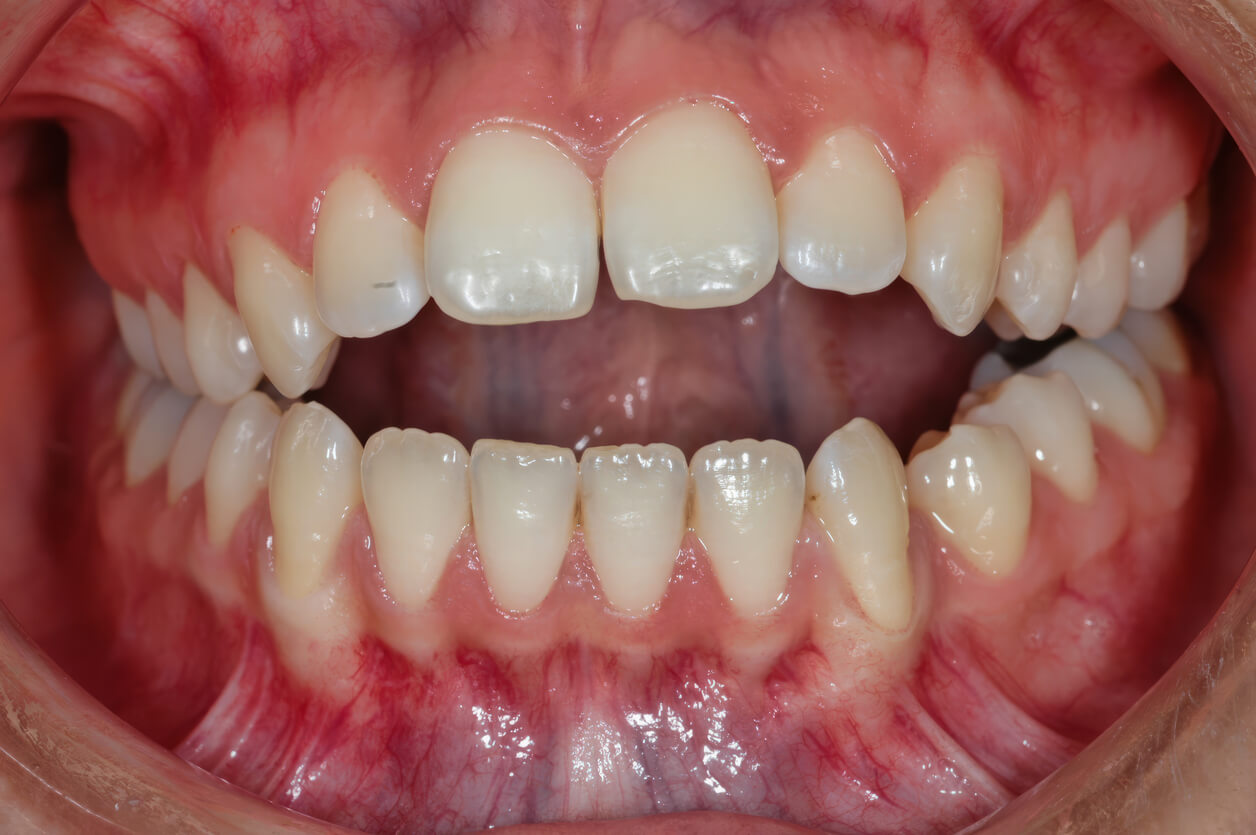

An open bite is a bite alignment issue where some teeth don’t make contact when you close your mouth. Instead of the top and bottom teeth meeting evenly, there’s a visible gap. That gap might be in the front, in the back, or along one side.

Anterior Open Bite

Anterior open bite happens when the upper and lower front teeth do not touch when the mouth closes, even though the back teeth may meet. This is the most noticeable type and often affects both appearance and function. People may have difficulty biting into foods like sandwiches or apples, and speech can sometimes be affected.